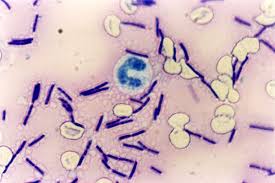

قیمت: 32٬000 تومان - دسته بندی فایل: پاورپوینتپاورپوینت باسیلوس آنتراسیس

فروش ویژه پاورپوینت حرفه ای باسیلوس آنتراسیس با تخفیف استثنایی فقط 42 هزار تومان تعداد اسلاید: 13 اسلاید